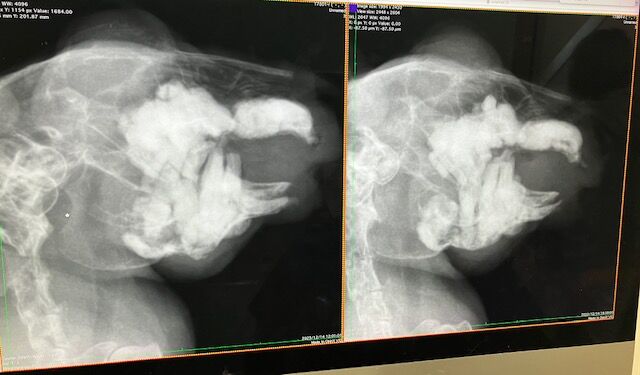

切歯不正咬合で通院はたくさんしましたが、

レントゲンなどは当初の去勢手術以降、機会がなかったので、

血液検査とともにしっかり健診させていただきました。

レントゲン

歯根への影響も見られず、共に良好でした